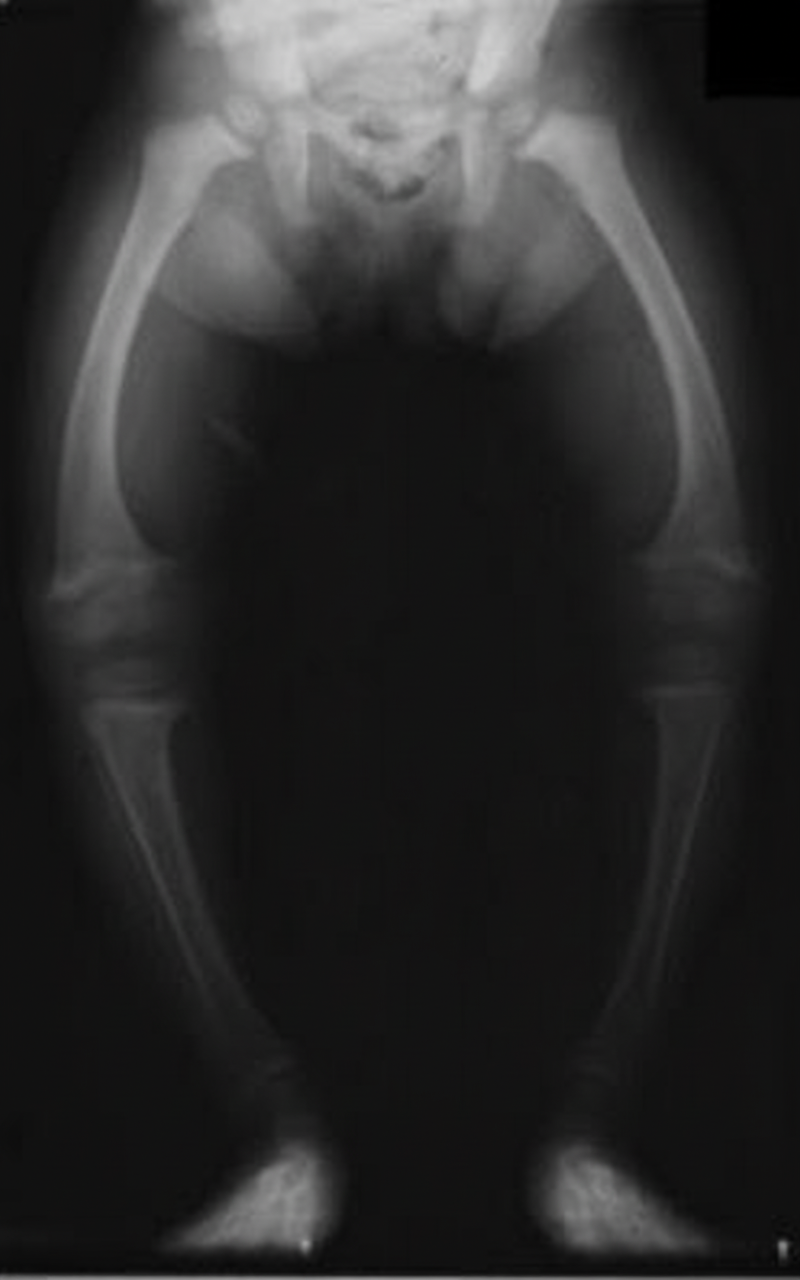

The most likely diagnosis in this child is:

Explanation: ***Rickets*** - **Widened, frayed, and cupped metaphyses** with **indistinct zone of provisional calcification** are pathognomonic X-ray findings of rickets due to defective mineralization. - **Bowing deformities** of long bones occur from weight-bearing on softened bones with inadequate **vitamin D** or **calcium**. *Scurvy* - Characterized by **sclerotic white line** (Frankel's line) and **corner sign** at metaphyses, not the cupping and fraying seen in rickets. - Shows **ground glass osteopenia** and **hemorrhages**, typically without the bowing deformities of rickets. *Salter Harris injury* - Represents **physeal fractures** with distinct fracture lines crossing the **growth plate**. - Shows **acute traumatic changes** with clear fracture patterns, not the chronic metabolic bone changes of rickets. *Greenstick fracture* - Shows **incomplete cortical break** with one side of the bone fractured and the other side bent. - Represents **acute trauma** in children with normal bone mineralization, lacking the metaphyseal changes of rickets.